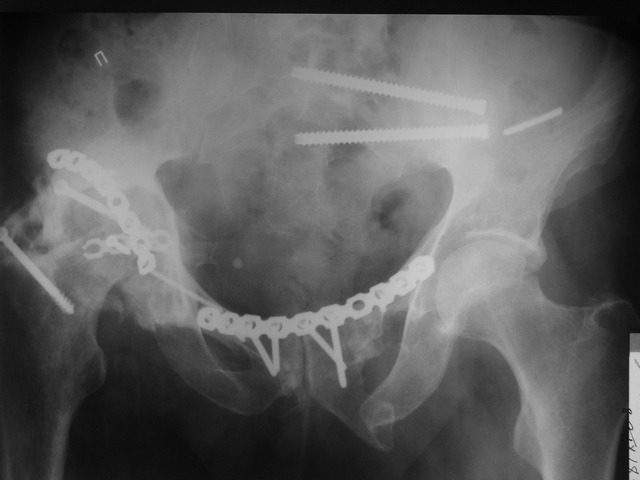

Пациент 49 лет, паровозная травма 23.2.2006, получил вертикальная нестабильное повреждение таза, разрыв левого крестцово-подвздошного сочленения, перелом лонной, седалищной костей слева, T-образный оскольчатый перелом правой вертлужной впадины с переломом заднего края, вывих правого бедра, посттравматическая пояснично-крестцовая плексопатия с обеих сторон, паралич мышц правой голени.

В день травмы - вправление вывиха, скелетное вытяжение, 14.3.2006 чрескостный остеосинтез таза. 20.4.2006 остеосинтез правой вертлужной впадины пластинами, осложнившийся нагноением межмышечной гематомы правой ягодичной области. Получал консервативное лечение, было достигнуто полное заживление раны. 24.7.2006 введены илиосакральные винты слева. С декабря 2006 года и по настоящее время ходит на костылях без опоры на правую ногу. Планируется THA. Помогите определиться с вариантом костной пластики? И какую укрепляющую конструкцию использовать?